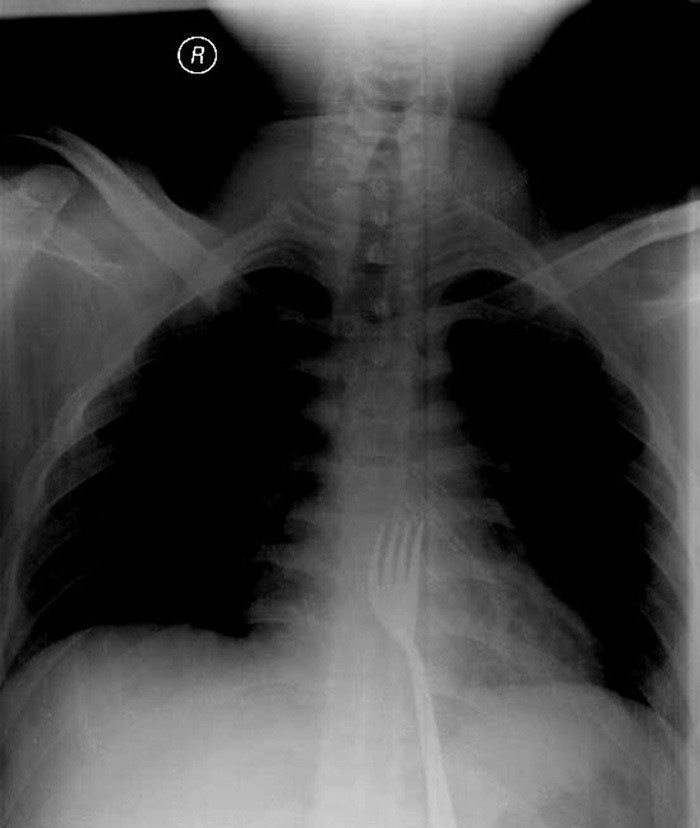

A fork was spotted in the man's stomach after his x-rays were taken, and was later on removed in a surgery.